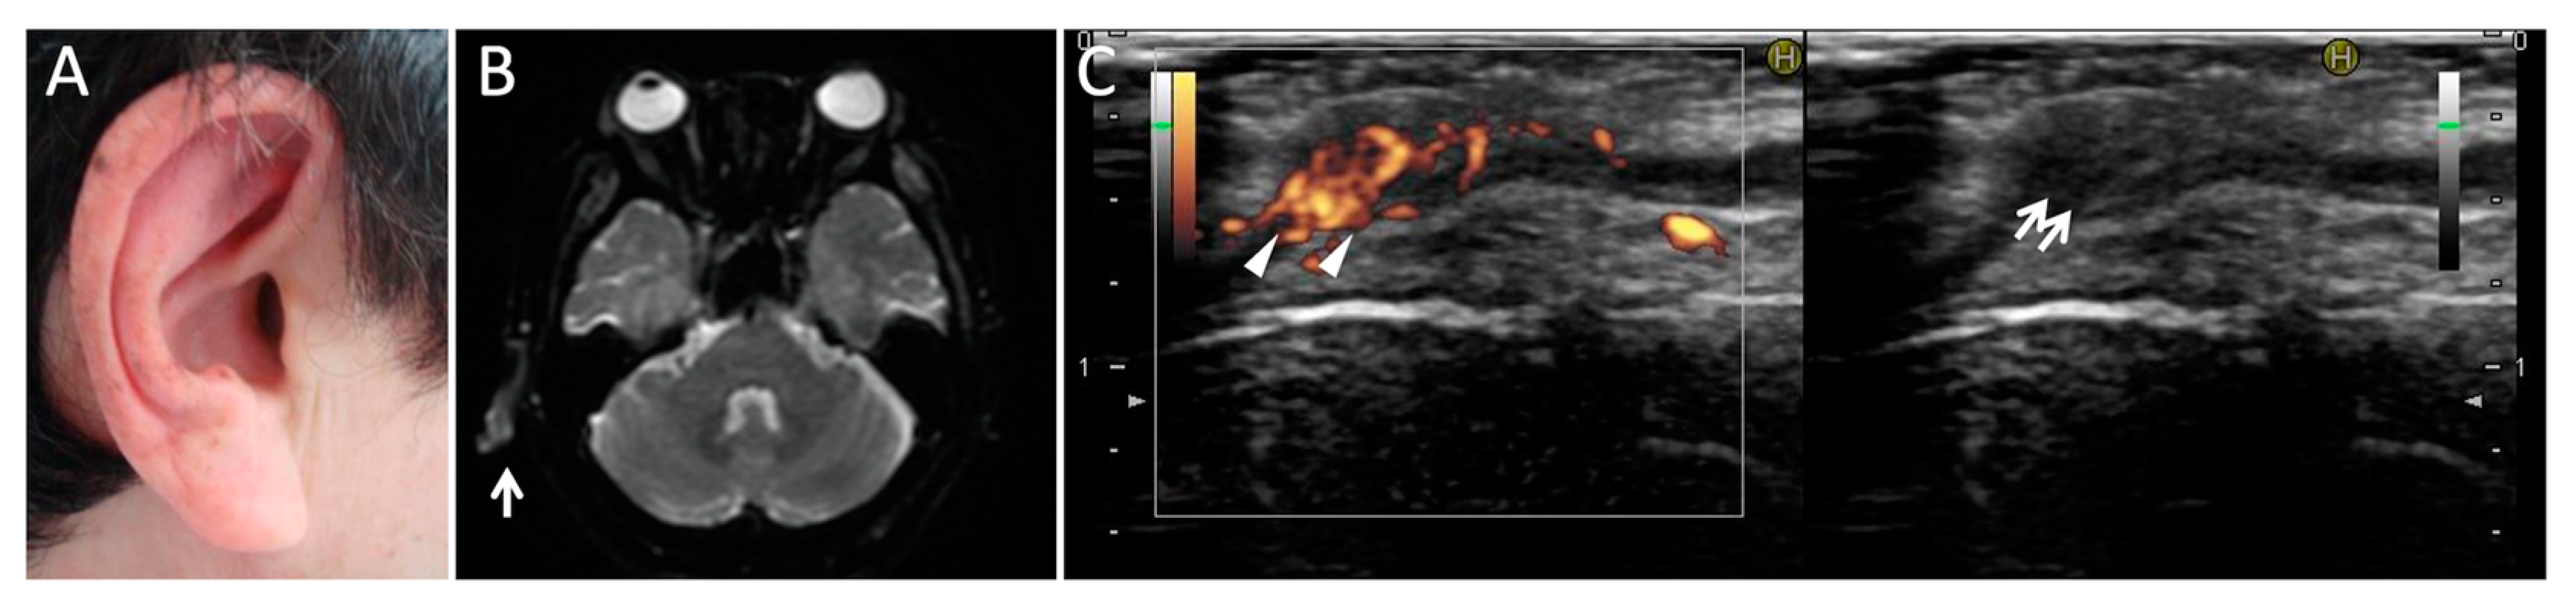

- Kuwabara, M.; Shimono, T.; Toyomasu, M.; Shioyama, M.; Mitsui, Y.; Yoshinaga, E.; Kawada, A.; Hosono, M.; Murakami, T.; Kusunoki, S. “Prominent ear sign” on diffusion-weighted magnetic resonance imaging in relapsing polychondritis. Radiat. Med. 2008, 26, 438–441. [Google Scholar] [CrossRef] [PubMed]

- Taniguchi, Y.; Nishikawa, H.; Nakayama, S.; Amano, E.; Terada, Y. Clinical implications of ultrasonography in monitoring disease activity of relapsing polychondritis. Rheumatology 2016, 55, 1250. [Google Scholar] [CrossRef][Green Version]

- Nakajima, I.; Taniguchi, Y.; Mizobuchi, T.; Kishimoto, T.; Fukushima, A.; Fukuda, K. Optic Neuropathy with Headache and Palpable Temporal Arteries Due to Hypertrophic Pachymeningitis Rather Than Giant Cell Arteritis. Ocul. Immunol. Inflamm. 2021, 2021, 1–4. [Google Scholar] [CrossRef]

- Taniguchi, Y.; Nishikawa, H.; Amano, E.; Fujimoto, S.; Terada, Y. Ultrasonographic findings as diagnostic and follow-up tool in cranial giant cell arteritis. QJM: Int. J. Med. 2017, 110, 851–852. [Google Scholar] [CrossRef]